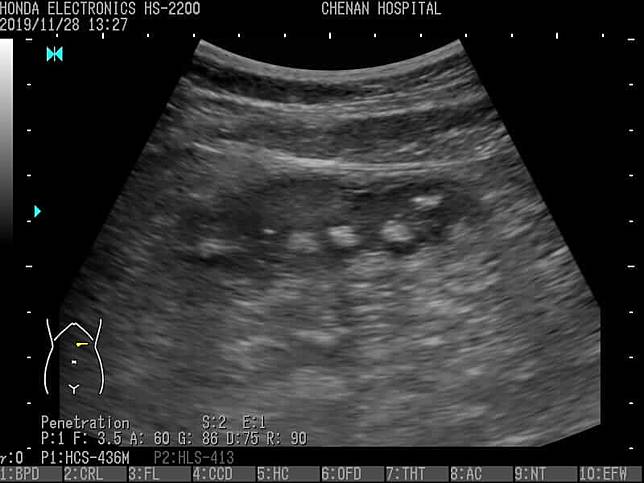

兒科醫師陳敬倫近日於臉書分享了一張照片,展示了空腹喝珍珠奶茶時,腹部超音波還可以清楚看到珍珠的輪廓。他表示,這幾個月遇到好幾位肚子痛的病患,都是前一天喝了一大杯珍珠奶茶的孩子,超音波檢查發現胃裡都是一顆一顆還沒消化的珍珠。

圖說:陳敬倫展示超音波下的腹中珍珠清晰可見。/圖片來源:臭寶爸 – 兒科陳敬倫醫師粉絲專頁